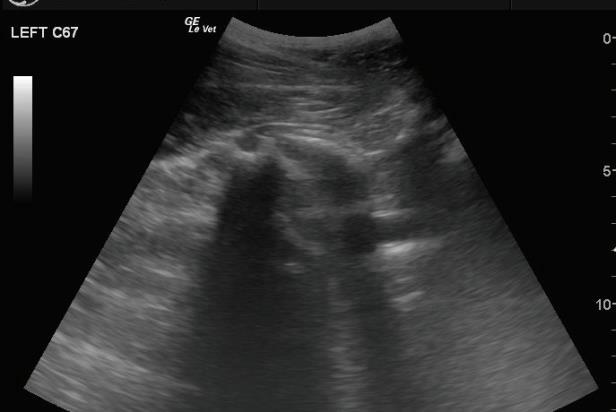

Often, a horse may demonstrate a faint lameness or radiographic fi ndings of the feet and navicular bone that are suspicious of pathology. Many exceptional equine athletes may exhibit mild issues in various areas, and clients are still interested in purchasing them. If additional radiographic images are not conclusive or not possible, nuclear scintigraphy may aid the decision process, if available. Th is is the buyer’s choice and fi nancial responsibility, but the seller must be willing to allow this semi-invasive procedure. Areas of increased radiopharmaceutical uptake (IRU) are characteristic of some structures in working horses and knowledge of this is required, 8 but this imaging modality can be extremely helpful in evaluating the significance of the fi ndings of other modalities such as radiography and ultrasound.

Radiographically abnormal navicular bones can sometimes be attributable to individual variation, and comparison between contralateral limbs is vital. However, a radiographically abnormal navicular bone that demonstrates intense IRU on scintigraphy is more likely to be indicative of inflammation and is of greater clinical significance than one with a normal uptake pattern.

Radiographic and ultrasonographic findings may be concerning for origin lesion. Nuclear scintigraphy can be useful in assessing the current state of in the proximal palmar/plantar metacarpus/tarsus and therefore providing valuable information by which the clinician may predict outcomes. An example follows in Fig.

Radiographic and ultrasonographic fi ndings may be concerning for a possible suspensory origin lesion. Nuclear scintigraphy can be useful in assessing the current state of activity in the proximal palmar/plantar metacarpus/tarsus and therefore providing valuable information by which the clinician may predict outcomes. An example follows in Figures 10 and 11.

image of the left proximal metatarsus demonstrating lysis and sclerosis at the suspensory ligament origin. Ultrasound indicates abnormal dorsal fiber pattern and an irregular bony origin.